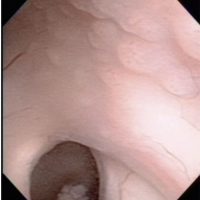

ジャーミノーマの内視鏡生検術のビデオ (endoscopic biopsy of germinoma) ここをクリックすると動画が見えます(3分46秒)

Peroperative view during endoscopic surgery in a boy with neurohypophyseal and pineal germinoma. There are numerous tiny nodules on the wall of right lateral ventricle.

These lesions are neither tumor CSF seeding nor dissemination. Germinoma cells always invades into subependymal glial tissue and spread to the whole ventricular system including the ovex. This has been called as subependymal infiltration (extension) of germinoma. Third ventriculostomy at the tuber cinereum in front of the mammillary bodies and tumor biopsy at the pineal lesion were shown.